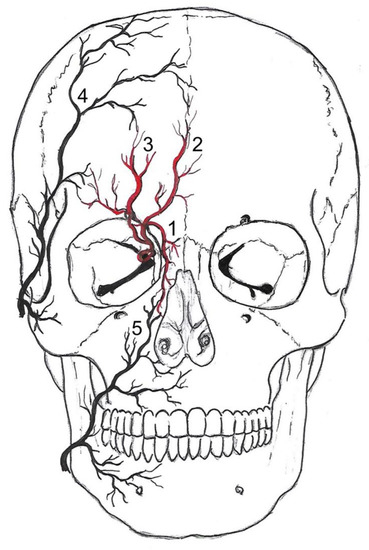

Figure 1. Anastomoses of the internal and external carotid arteries. Vessels drawn in red (1–3) belong to the internal carotid drainage and vessels depicted in black (4, 5) belong to external carotid artery drainage. The dorsal nasal artery (1) and the supratrochlear artery (2) are the terminal branches of the ophthalmic artery—a branch of the internal carotid artery. The supraorbital artery (3) is a branch of the intraorbital ophthalmic artery and passes through the supraorbital foramen. It anastomoses within the scalp with the superficial temporal artery (4) and the supratrochlear artery. The supratrochlear artery pierces the orbital septum at the medial corner of the orbit superiorly. It anastomoses with the superficial temporal artery and the contralateral supratrochlear artery. The dorsal nasal artery pierces the septum orbitale above the medial palpebral ligament. It anastomoses with the angular termination of the facial artery (5) and the contralateral dorsal nasal artery.

There is a watershed (border zones of distinct perfusion) in the supraorbital and infraorbital region between the distal branches of the ICA and ECA (Figure 1). It has been long established that the detection of flow changes in the supraorbital artery (SOA) and supratrochlear artery (STA) indicate severe carotid artery obstruction [5]. The ophthalmic artery is usually supplied by the intracranial portion of the ICA. Its terminal branches—the STA, the dorsal nasal artery (DNA), and the SOA—anastomose with the superficial temporal artery and the angular termination of the facial artery. If the extracranial or infraophthalmic intracranial ICA is significantly stenosed, the resulting pressure gradient results in a shift of the watershed towards the intraorbital arteries, with a retrograde flow in the STA and SOA. Normal ophthalmic flow can be maintained if the obstruction is compensated by anterior or posterior communicating arteries [6]. Proximal occlusions are more effectively compensated by collateral arteries than distal arteries.